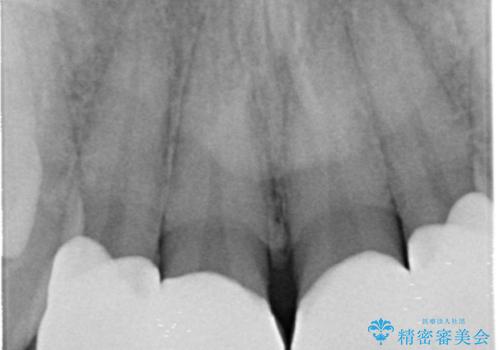

全て神経は取らずに、削りました。

- 天然歯を削ります

- 硬い素材は天然歯を傷つけてしまう場合があります

- かみ合わせや歯ぎしりが強すぎる方はセラミックが割れてしまう可能性があります